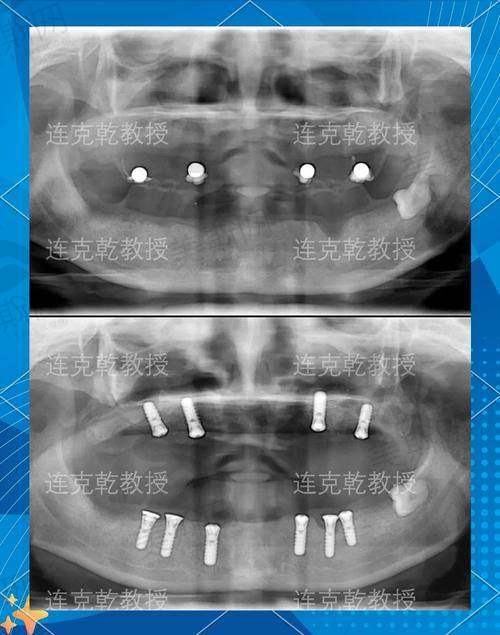

1. 牙齿种植:开展即刻种植、微创种植、全口/半口种植修复等技术,采用数字化导板精细定位,缩短手术时间,减少创伤,支持单颗、多颗及全口缺失牙修复,适配韩国登腾、德国ICX、瑞士ITI等多种种植体品牌。

江西九江中山口腔医院的核心特色技术之一是数字化精细种植技术,该技术通过口腔CT三维扫描,构建患者口腔三维模型,医生在计算机上模拟种植过程,制定个性化种植方案,并利用3D打印技术制作手术导板,确保种植体植入的角度、深度和位置精细无误,误差控制在0.5mm以内。相比传统种植技术,数字化种植减少了手术创伤,无需翻瓣,术后肿胀轻、修复快,单颗牙种植手术时间可缩短至30分钟,实现“即拔即种即修复”,尤其适合牙槽骨条件较好的患者,当天即可修复牙齿功能。